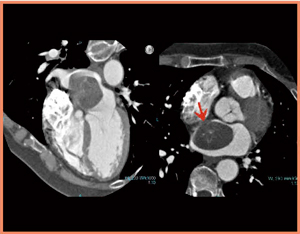

・症例6:70歳代,男性。糖尿病のフォロー中に,心エコーで左室躯出率(EF)の低下が指摘された。

冠動脈CTAで,LAD領域に境界域の狭窄病変が認められた。負荷心筋パーフュージョンCTでは,LAD領域に若干の低下域があるものの,重度ではないことがわかった(図8)。この患者は心筋シンチグラフィでも同様の所見であり,現在フォロー中である。

図8 症例6:LAD狭窄症例の心筋パーフュージョンCT